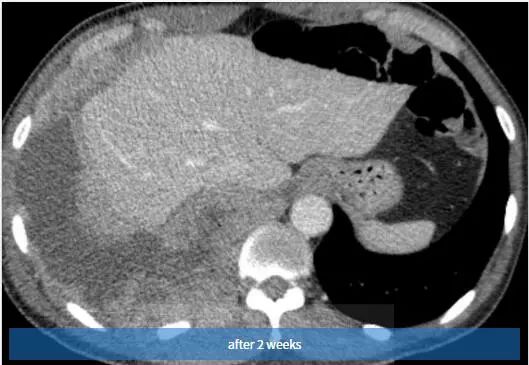

图3 2周后,随访胸片示右胸弥漫性阴影和胸腔积液。也可见引流管。

图4~6 2周内随访的对比增强轴位CT扫描示右半胸有大量多发性胸腔积液,弥漫性胸膜增厚和多灶性胸膜肿块。